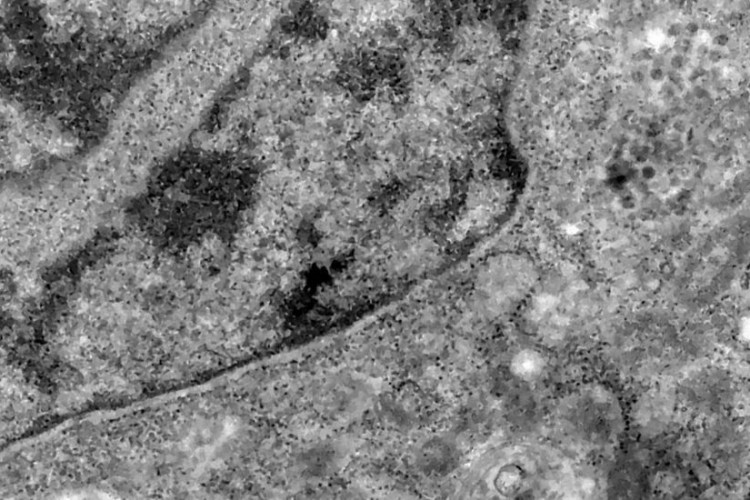

Nos casos analisados, constatou-se que a variante é portadora de dezenas de mutações genéticas que podem afetar os índices de contágio e de letalidade. A OMS, entretanto, afirmou que ainda não há estudos suficientes para afirmar as propriedades da Ômicron, mas que já existem esforços científicos acelerados para estudar as amostras. Um time de cientistas de universidades da África do Sul está decodificando o genoma da Ômicron, juntamente com dezenas de outras variantes do novo coronavírus.

Tulio de Oliveira, diretor do Centro para Respostas e Inovações Epidêmicas da universidade de KwaZulu-Natal, afirmou em coletiva de imprensa que a variante Ômicron possui “uma constelação incomum de mutações”. A variante Delta, por exemplo, possuía duas mutações em relação à cepa original do novo coronavírus, enquanto a Ômicron possui cerca de 50 - 30 delas localizadas na proteína Spike, responsável por infectar células saudáveis, explicou o brasileiro.